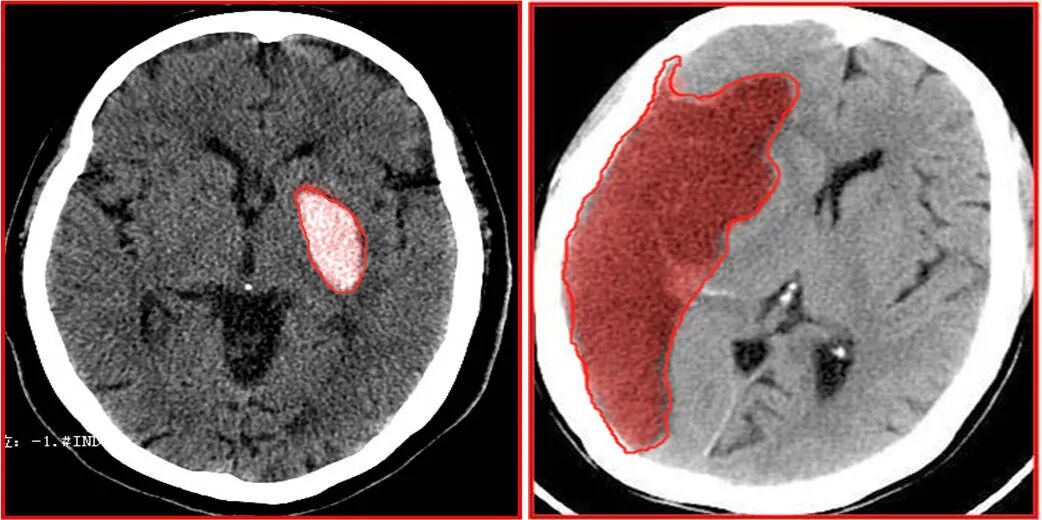

颅脑CT